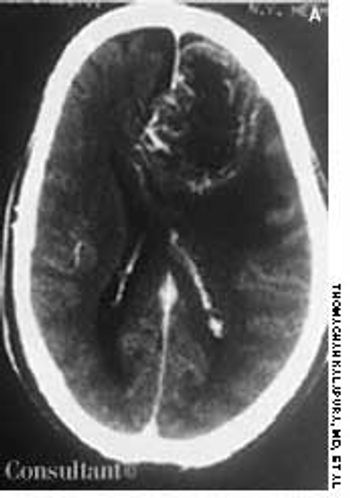

A 57-year-old man was brought to the emergency department with severe bifrontal headache, which he had had for 3 weeks. Family members reported that the patient exhibited episodes of confusion and loss of recent memory since the onset of the headache.